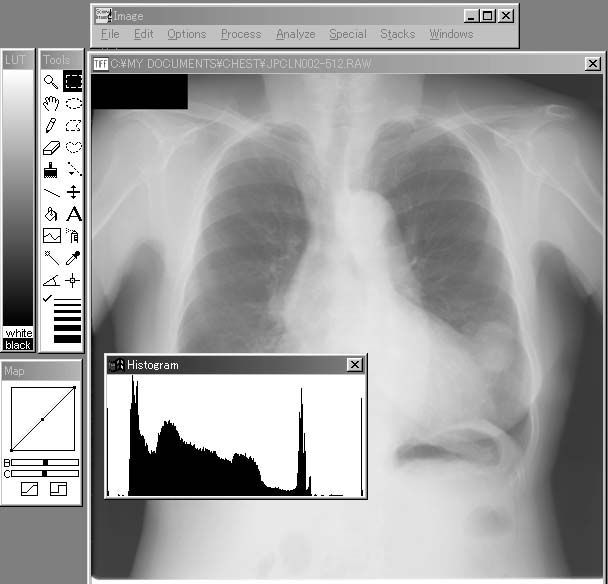

B. Show Histogram(ヒストグラムの表示)

「Show Histogram」では,現在表示している画像のヒストグラムを計算し,表示する(図5-3).このヒストグラムは,横軸が画素値,縦軸がその頻度であり,「Measure」と同様に,領域選択ツールで領域を決め,その領域内だけのヒストグラムを作成することも可能である.

図5-3 「Show Histogram」による256階調のChest画像全体のヒストグラムの表示例